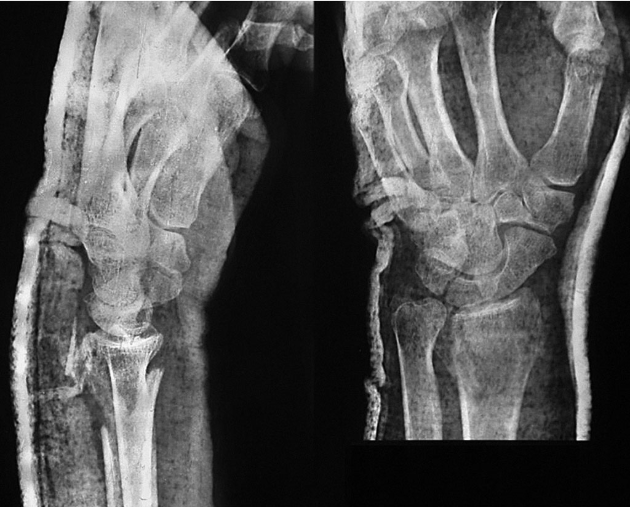

术前拍腕关节正、侧位X线片,腕关节冠状位、矢状位和水平位CT(图2-2)此患者骨缺损和无法闭合复位的骨片均在背侧,宜采用背侧入路,复位,植骨,固定。取患肢前臂远端桡背侧纵切口(图2-3)从伸拇长肌腱和桡侧伸腕长、短肌之间进入,注意保护血管神经和肌腱,显露清理折端骨缺损区域和背侧移位的骨片(图2-4复位,植骨,外固定架超关节固定(图2-5、图2-6)。术中透视骨折复位固定满意(图2-7),术后拍X线片证实(图2-8)。此手术的优点在于避免了局部存在内固定物的刺激,避免二期切开取出固定物所致的再次损伤。

图2-5 外固定架超关节固定

图2-6 显示植骨和骨片复位

图2-7 术中透视示骨折复位、固定、植骨满意

图2-8 术后X线片示骨折复位、固定、植骨满意